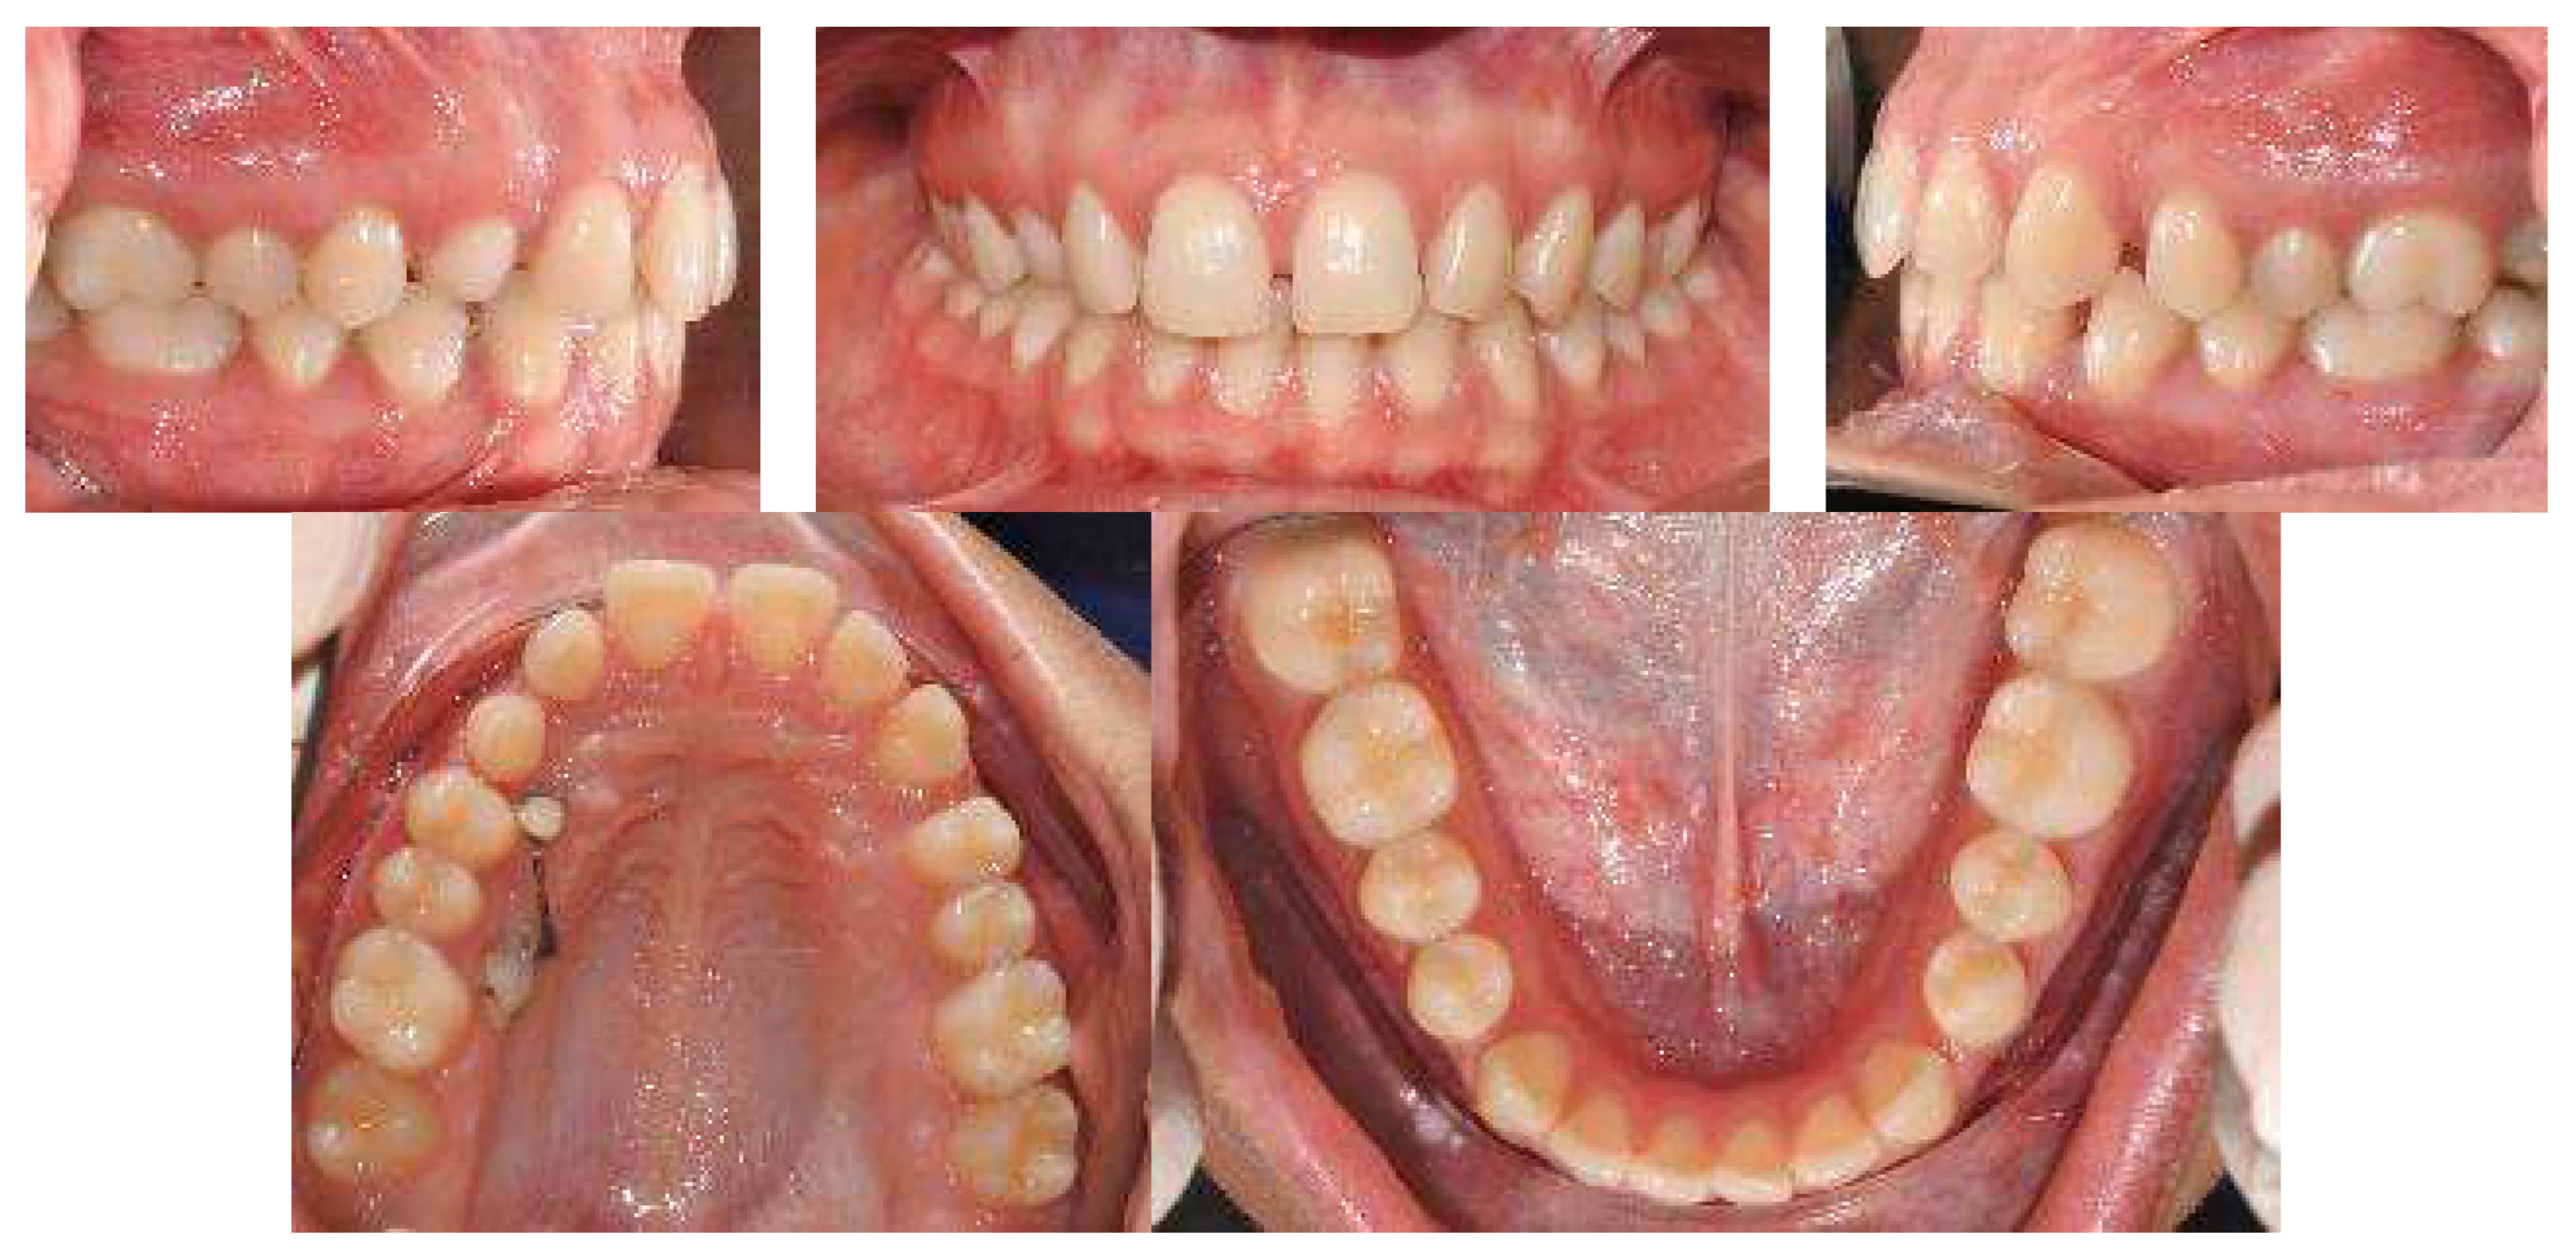

An 18-year-old female patient was referred, complaining of unpleasant smile. She presented good general health and no systemic or congenital diseases. From a frontal view, the patient presented a well-proportioned three-thirds of her face and no evidence of asymmetry. From the lateral view, the profile appeared convex with well-represented nasolabial angle, labiomental sulcus, and lip competence. Intraorally, the patient showed a Class II malocclusion with the molar Class I relationship, edge to edge canine relationship on both sides, increased overjet, overbite, and the retention of the 63. Panoramic, lateral headfilm, and dental cast records were taken (Figure 11).

An 18-year-old female with dentoskeletal Class II with impacted upper left canine before treatment.

The initial cephalometric analysis showed a skeletal Class I relationship (ANB, +2.6°) and mesodivergent pattern with the proclination of the upper (I/ANS-PNS 118.8°) and lower (i/GoGn:102.2°) incisors. All the radiographic findings, the age of the patient, the prolonged deciduous retention, and the risk of root resorption of the adjacent tooth, led clinicians to conclude that the permanent canine would not erupt properly without intervention (Table 2).

The position of the impacted canine showed an alpha angle of 58° and the Ericson and Kurol II sector classification. No clinical symptoms on articular examination were detected (Figure 12).

Pre-treatment panoramic X-ray with the evaluation of alpha angle and sector according to the Ericson and Kurol classification.